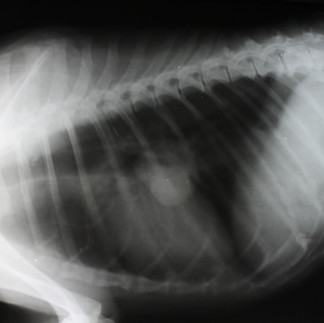

Breast cancer is best diagnosed with a surgical biopsy. Blood work and radiographs (x-rays) are usually recommended to help determine if the cancerous cells have spread to other parts of the body.

Early detection and surgically removing the masses is the best treatment option. Before performing surgery, it is recommended that blood work and radiographs (x-rays) are done. Chest radiographs are important to check for any cancer that could have spread to the lungs, and abdominal x-rays may show signs of enlarged lymph nodes. If the radiographs show no evidence of spreading, the pet has a better prognosis. Submission of the tissue for microscopic examination will determine if the tumours have been completely removed. Surgical removal of the tumour with the regional lymph node will increase disease-free time but, in cases of malignancy, may not increase survival time.